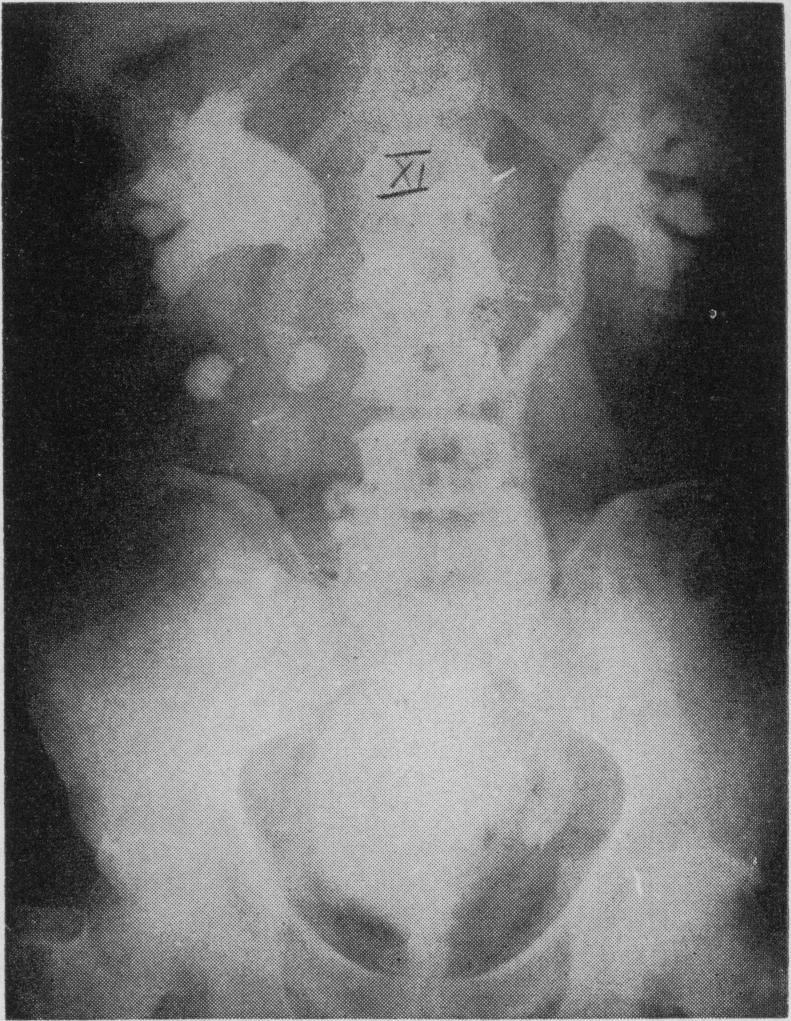

Sigmoid segment substitutes for bladder.